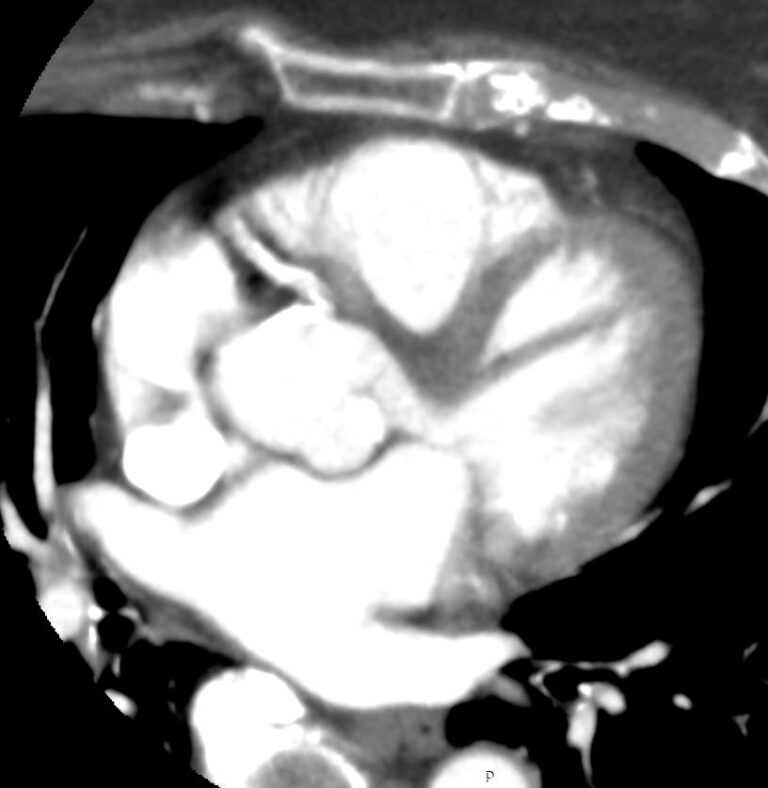

Мультиспиральная КТ сосудов сердца (коронарография) является лучевым методом исследования состояния кровеносных сосудов сердца. Это значит, что для получения изображения сосудов сердца используется рентгеновское излучение.

В нашей клинике КТ-коронарография выполняется на современных мультиспиральных компьютерных томографах последнего поколения TOSHIBA AQUILION. Трубка томографа испускает рентгеновские лучи, непрерывно вращаясь вокруг области исследования. Аппараты оборудованы увеличенным количеством детекторов, которые улавливают сигналы от внутренних органов после прохождения рентгеновских лучей. С помощью цифровых приложений полученные результаты преобразуются в трехмерные изображения сосудистой системы сердца.

Для того, чтобы качественно визуализировать коронарные артерии пациенту внутривенно вводится контрастный препарат на основе йода. Благодаря способности контраста поглощать рентгеновские лучи, коронарные сосуды ярко контрастируют на фоне окружающих тканей. Метод КТ-коронарографии дает информацию о точной локализации стеноза, позволяет судить о степени сужения коронарных артерий, позволяет выявить аномалии развития сосудов сердца, а также оценить состояние установленных в просвет артерий стентов, функционирование шунтов после операции аортокоронарного шунтирования. При этом аппараты обеспечивают минимальную дозу рентгеновского облучения для организма человека.

Мультиспиральная КТ сосудов сердца позволяет оценить анатомические особенности строения коронарных артерий, выявить участки сужения просвета сосудов, изучить структуру атеросклеротической бляшки, выявить кальциноз стенок сосудов и клапанов сердца.